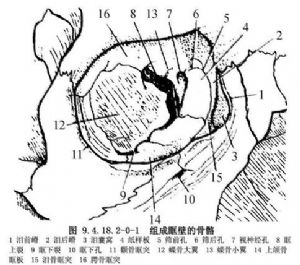

骨性眼眶是由筛、额、泪、上颌、颚、蝶和颧骨共7块骨组成,约呈四面锥体,尖端为视神经孔,容纳并保护眼球及其相关的组织(图9.4.18.2-0-1,9.4.18.2-0-2)。

鼻窦共有四对,均与眼眶相邻。组成眶顶的额骨在两眶上壁的内侧二分之一部有额窦,组成眶内侧壁的为泪骨和筛骨,内有筛窦。蝶骨内的蝶窦与视神经孔只隔一薄板。而作为眶底主要部分的上颌骨内为上颌窦。这样全部四对鼻窦包围在眶眶上、内、下三面(图9.4.18.2-0-3,9.4.18.2-0-4)。

眶上壁:前部为额骨眶面,后部为蝶骨小翼。额窦位于眶面前部的内侧一半,在眶缘内上角向下延伸到额筛缝。眶上壁前内部实为额窦的下壁。

眶内侧壁:由蝶骨体、筛骨和泪骨组成,后部的视神经管内侧壁为蝶窦,前面的大部分为筛窦。因此,眶内侧壁也就是蝶骨、筛骨和泪骨的眶面薄壁。

眶下壁:前外方小部分为从眶外壁延伸下来的颧骨眶面,内侧大部由上颌骨眶面形成,而眶面下便是上颌窦。眶下壁内侧大部分是上颌窦的顶。